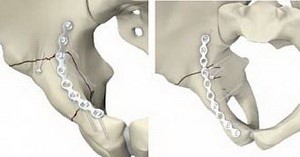

После стабилизации всех жизненно важных функций при не осложненном переломе хирург приступает к непосредственному лечению переломов костей таза. Выбор тактики ведения пациента при переломах зависит от тяжести состояния, наличия осложнений.

- Иммобилизация простых переломов без смещения проводится на щите или в специальном гамаке. Состояние иммунной системы, наличие сопутствующих заболеваний, возраст влияют на то, сколько заживает перелом. В среднем этот срок составляет 3 месяца, но может быть и больше.

- Переломы со смещением – прямое показание к скелетному вытяжению. Через кость проводятся спицы, которые фиксируются снаружи на специальной рамке. Такая процедура позволяет оттянуть отломки кости друг от друга. Как правило, дальше следует оперативное вмешательство.

- Операция состоит из фиксации всех частей таза с помощью спиц, металлических пластин, винтов, а также стержней в аппарате внешней фиксации. После остеосинтеза показана иммобилизация на протяжении 3-4 месяцев.